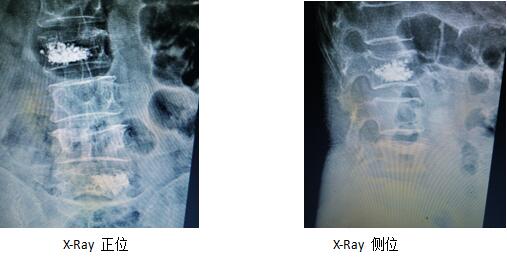

術(shù)前影像學片